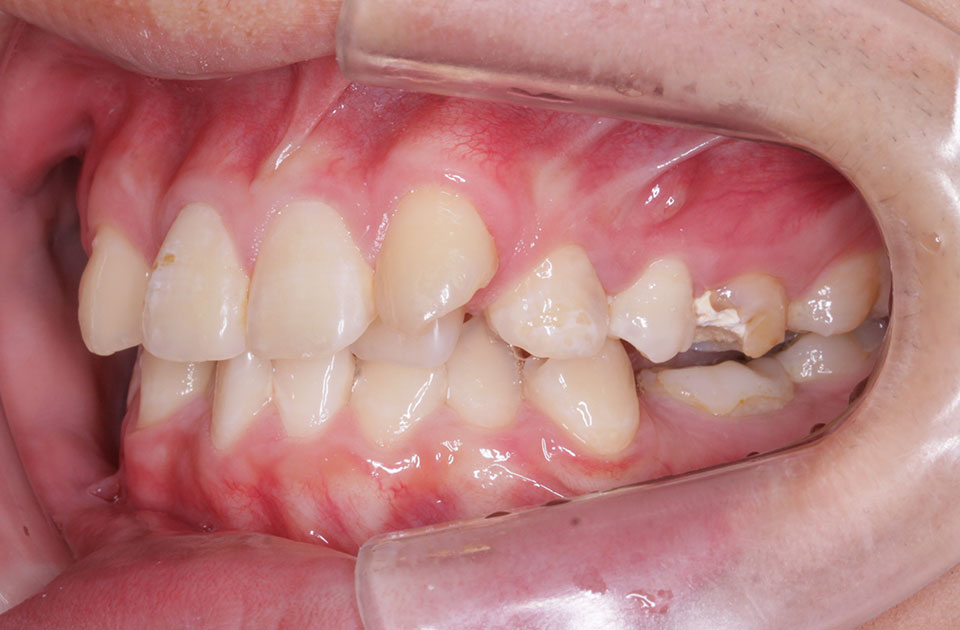

矯正前 右側

矯正後 右側